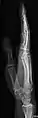

Extremities

A projectional radiograph of an extremity confers an effective dose of approximately 0.001 mSv, comparable to a background radiation equivalent time of 3 hours.[16]

The standard projection protocols in the UK are:[15]

- Humerus - AP and Lateral

- Elbow - AP and Lateral. Radial head projections available on request

- Radius and Ulna - AP and Lateral

- Wrist - DP and Lateral

- Scaphoid - DP with Ulna deviation, Lateral, Oblique and DP with 30° angulation

- Hand - DP and Oblique

- Fingers - DP and Lateral

- Thumb - AP and Lateral